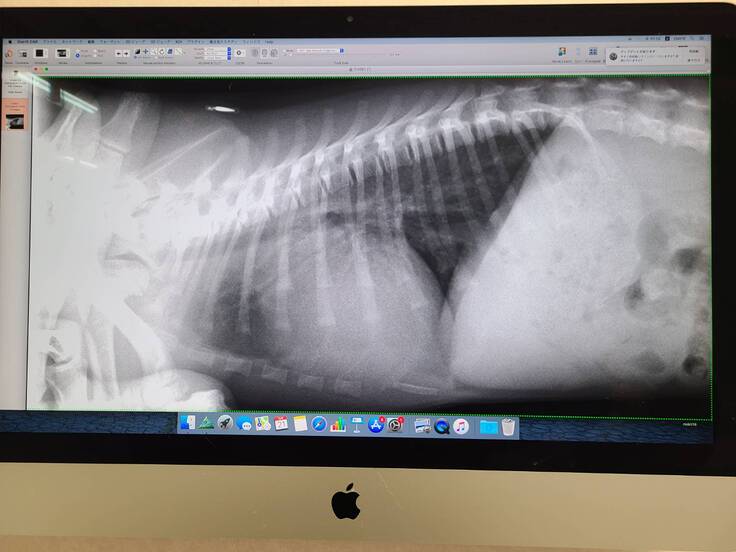

▲そらのレントゲン写真です。

掲載許可はいただいています。